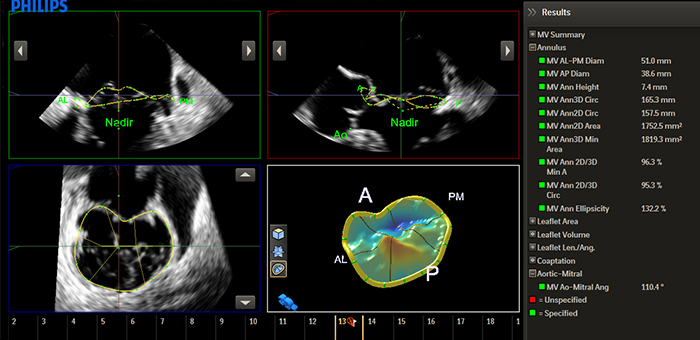

Anatomical Intelligenceは患者の超音波データを見て、3D解剖学的モデルを使用するシステムインテリジェンスを適用し、簡単で再現性の高い検査結果を生み出します。高度な臓器モデル化、画像スライス、実績のある定量化機能によって超音波検査を再現性を高めることによってサポートし、同時に今日のヘルスケア環境の経済的および臨床的課題に対応する新しいレベルの臨床情報を提供します。

HeartModelᴬ⋅ᴵ⋅は、最上位の優れた新しいAnatomically Intelligent Ultrasound(AIUS)アプリケーションで、1つのLive 3Dボリュームから左室(LV)および左房(LA)のボリュームと駆出率を自動的に検出、セグメント化、定量化します。HeartModelᴬ⋅ᴵ⋅は日々の心エコー検査において最新の自動定量化、3D表示、確実な再現性、および最大82%の時間短縮を実現します。

Anatomical Intelligenceは、EPIQ、Affiniti、EchoNavigatorなどをはじめとするフィリップスのイメージングソリューションで使用されています。解剖学的構造の異常などを迅速かつ確実に特定し、治療法の決定やインターベンション時のガイドに役立っています。

EPIQ CVxは、飛躍的に進歩した機能をもつ循環器用超音波診断ソリューションです。処理能力の向上、優れた鮮明さと高い分解能による卓越したイメージング、検査効率の改善、アナトミカル・インテリジェンス(AIUS)による堅牢で再現性の高い新たな定量化手法により、より良い検査を行うためにサポートします。